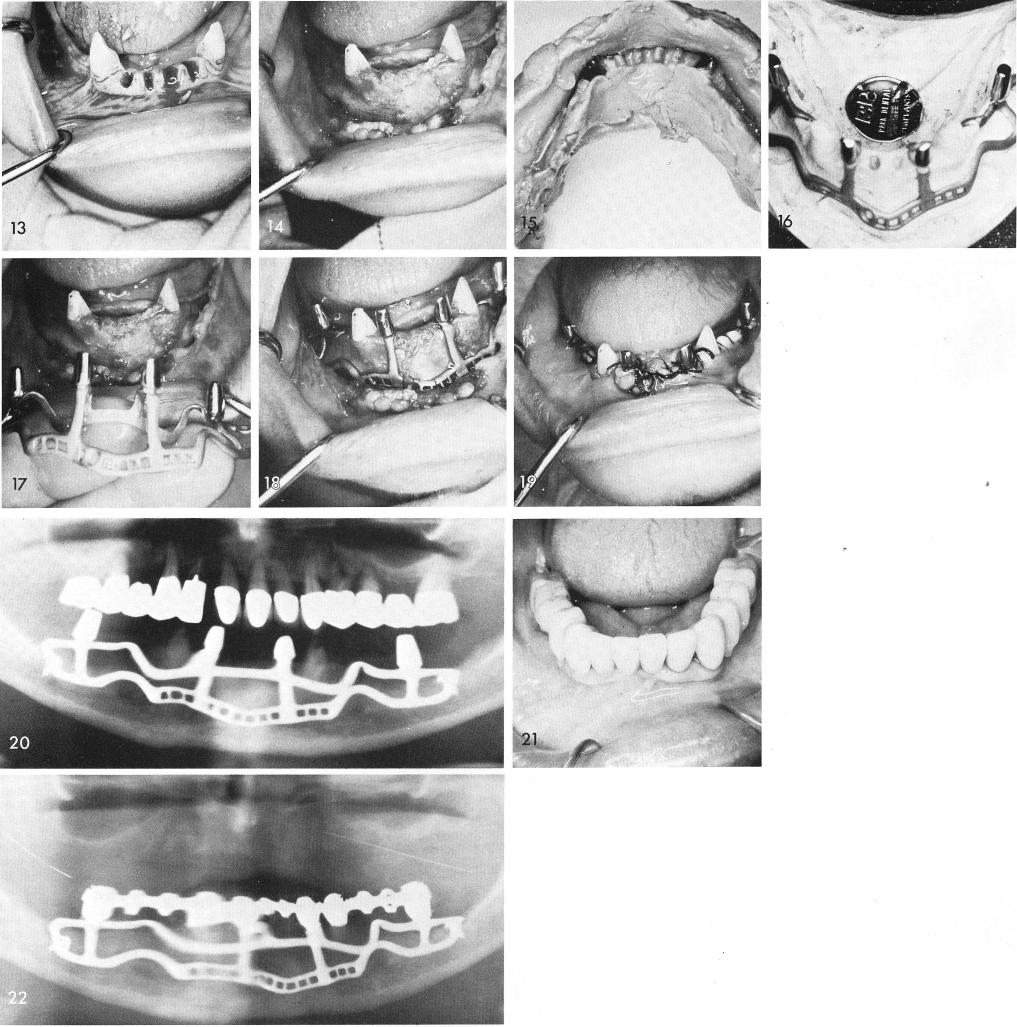

The four incisors because of periodontal problems had to be extracted, fig. 13. Six months later the surgery for the impression was accomplished. The teeth remaining should always be prepared for full crown coverage prior to the impression, fig. 14. The impression, fig. 15, and implant, fig. 16. The implant is fitted over the bone, figs. 17, 18, and the tissues are sutured, fig. 19. An immediate post-operative x-ray shows the implant and teeth, fig. 20. The prosthesis is fixed and cemented into position, fig. 21. The final x-ray, fig. 22.

1 The mandibular subperiosteal implant is fitted over the bone